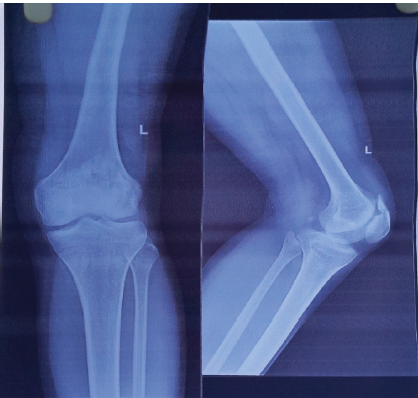

Now we got a 3-year follow-up with a full range of motion, can do squatting on his own, and no pain at the operated site. However, as we saw the recent X-ray of the patient, we discovered a spike of bone developing at the upper pole of the patella where we took the stitches (Fig. 5).

Figure 5: Recent X-ray showing the bony spike.

In this report, we present a case of a rare traumatic QTR in the adolescent age group, which was managed by primary open repair. Excellent functional outcomes with no extensor lag and excellent restoration of the flexion arch of motion are reported, except the bony spike that we saw recently in the X-ray. The etiology of this particular X-ray pattern may be due to the stitches we took at the proximal pole of the patella directly. Orthopaedic surgeons performing these reconstructions should know that these X-ray findings can occur.

We reported a case of adolescent traumatic quadriceps repair, treated with primary open repair. Follow-up showed no disability from patient’s point of view. Our study has post-operative MRI, which shows intact quadriceps and no other abnormalities. The etiology of this particular X-ray pattern may be due to the stitches we took at the proximal pole of the patella directly.